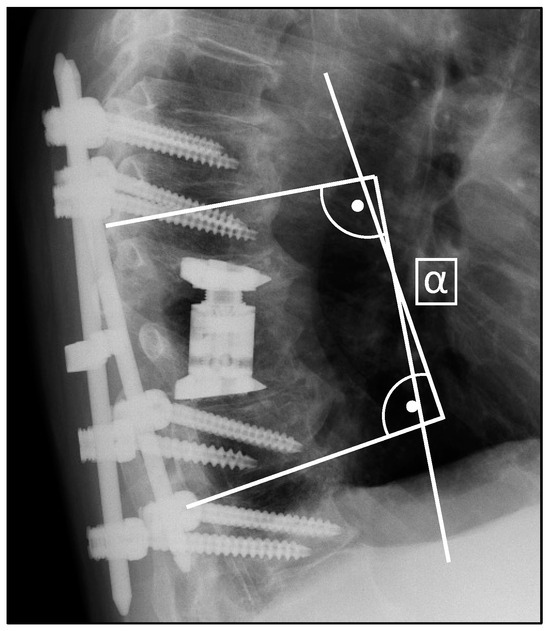

2.3. Radiological Assessment